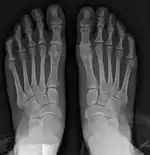

- For recurrence correction after osteotomy procedure (Fig. 8)

Late deformity recurrence can happen after osteotomy (bone-breaking) procedures because osteotomy surgeries do not specifically stabilize first metatarsal bone.